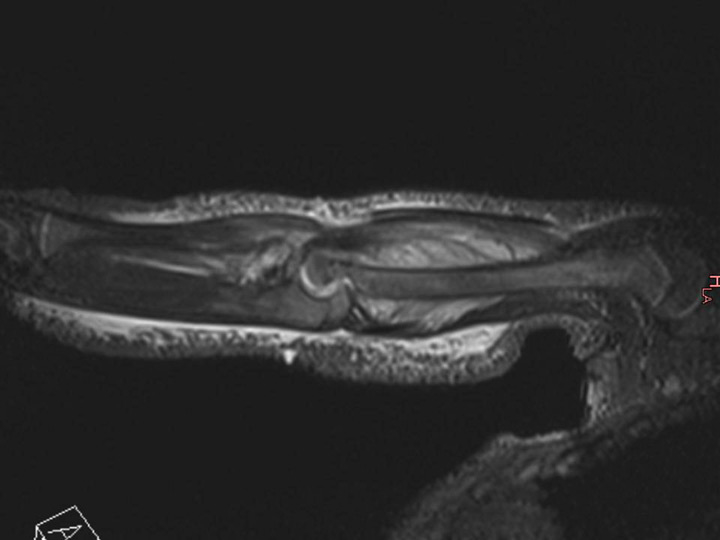

Figure 3

Magnetic resonance imaging (MRI) of the distal femur of a 17-month-old boy, which showed a normal appearance on plain radiographs. MRI demonstrated a lytic lesion of the distal femoral epiphysis with an important abscess of the soft surrounding tissues. Specific cultures confirmed tuberculosis.